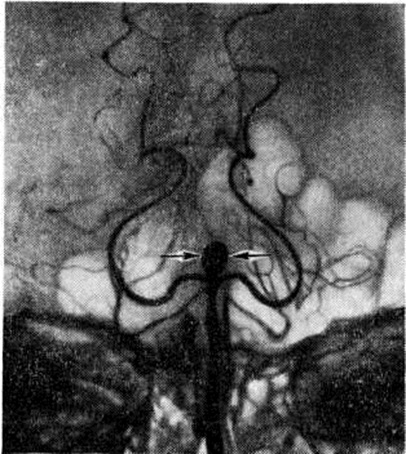

Эпидуральные и субдуральные кровоизлияния в подавляющем большинстве случаев наблюдаются при черепно-мозговой травме (смотри полный свод знаний). Субарахноидальное кровоизлияние возникает наиболее часто вследствие разрыва врождённых мешотчатых или артериовенозных аневризм (смотри полный свод знаний: Аневризма сосудов головного мозга), располагающихся чаще всего в местах разветвления сосудов основания головного мозга (рисунок 1). Некоторые инфекционные болезни, например, грипп (смотри полный свод знаний), геморрагические лихорадки (смотри полный свод знаний) и другие, при тяжёлом течении иногда могут сопровождаться Подоболочечные кровоизлияния Нередко Подоболочечные кровоизлияния возникают в пожилом возрасте у больных атеросклерозом при разрыве склерозированных сосудов мозговых оболочек, а также при хронический воспалительных процессах в твёрдой оболочке мозга, сопровождающихся поражением вен (смотри полный свод знаний: Пахименингит). Развитию Подоболочечные кровоизлияния способствуют заболевания печени, крови, авитаминозы, приводящие к развитию геморрагического синдрома. В ряде случаев Подоболочечные кровоизлияния могут сопутствовать кровоизлияниям в вещество головного мозга при гипертонической болезни, располагаясь часто в задней черепной ямке на поверхности полушарий мозжечка или ствола мозга (рисунок 2, 3). Скопление крови в задней черепной ямке нарушает отток цереброспинальной жидкости и создаёт условия для развития окклюзионной гидроцефалии (смотри полный свод знаний) и отёка мозга (смотри полный свод знаний: Отёк и набухание головного мозга). Вызвать Подоболочечные кровоизлияния могут резкие наклоны туловища, физическая нагрузка, эмоциональное напряжение, сопровождающиеся значительным подъёмом АД.

Рис. 1.

Ангиограмма базилярной и задних мозговых артерий головного мозга с аневризмой бифуркации базилярной артерии (указана стрелками).